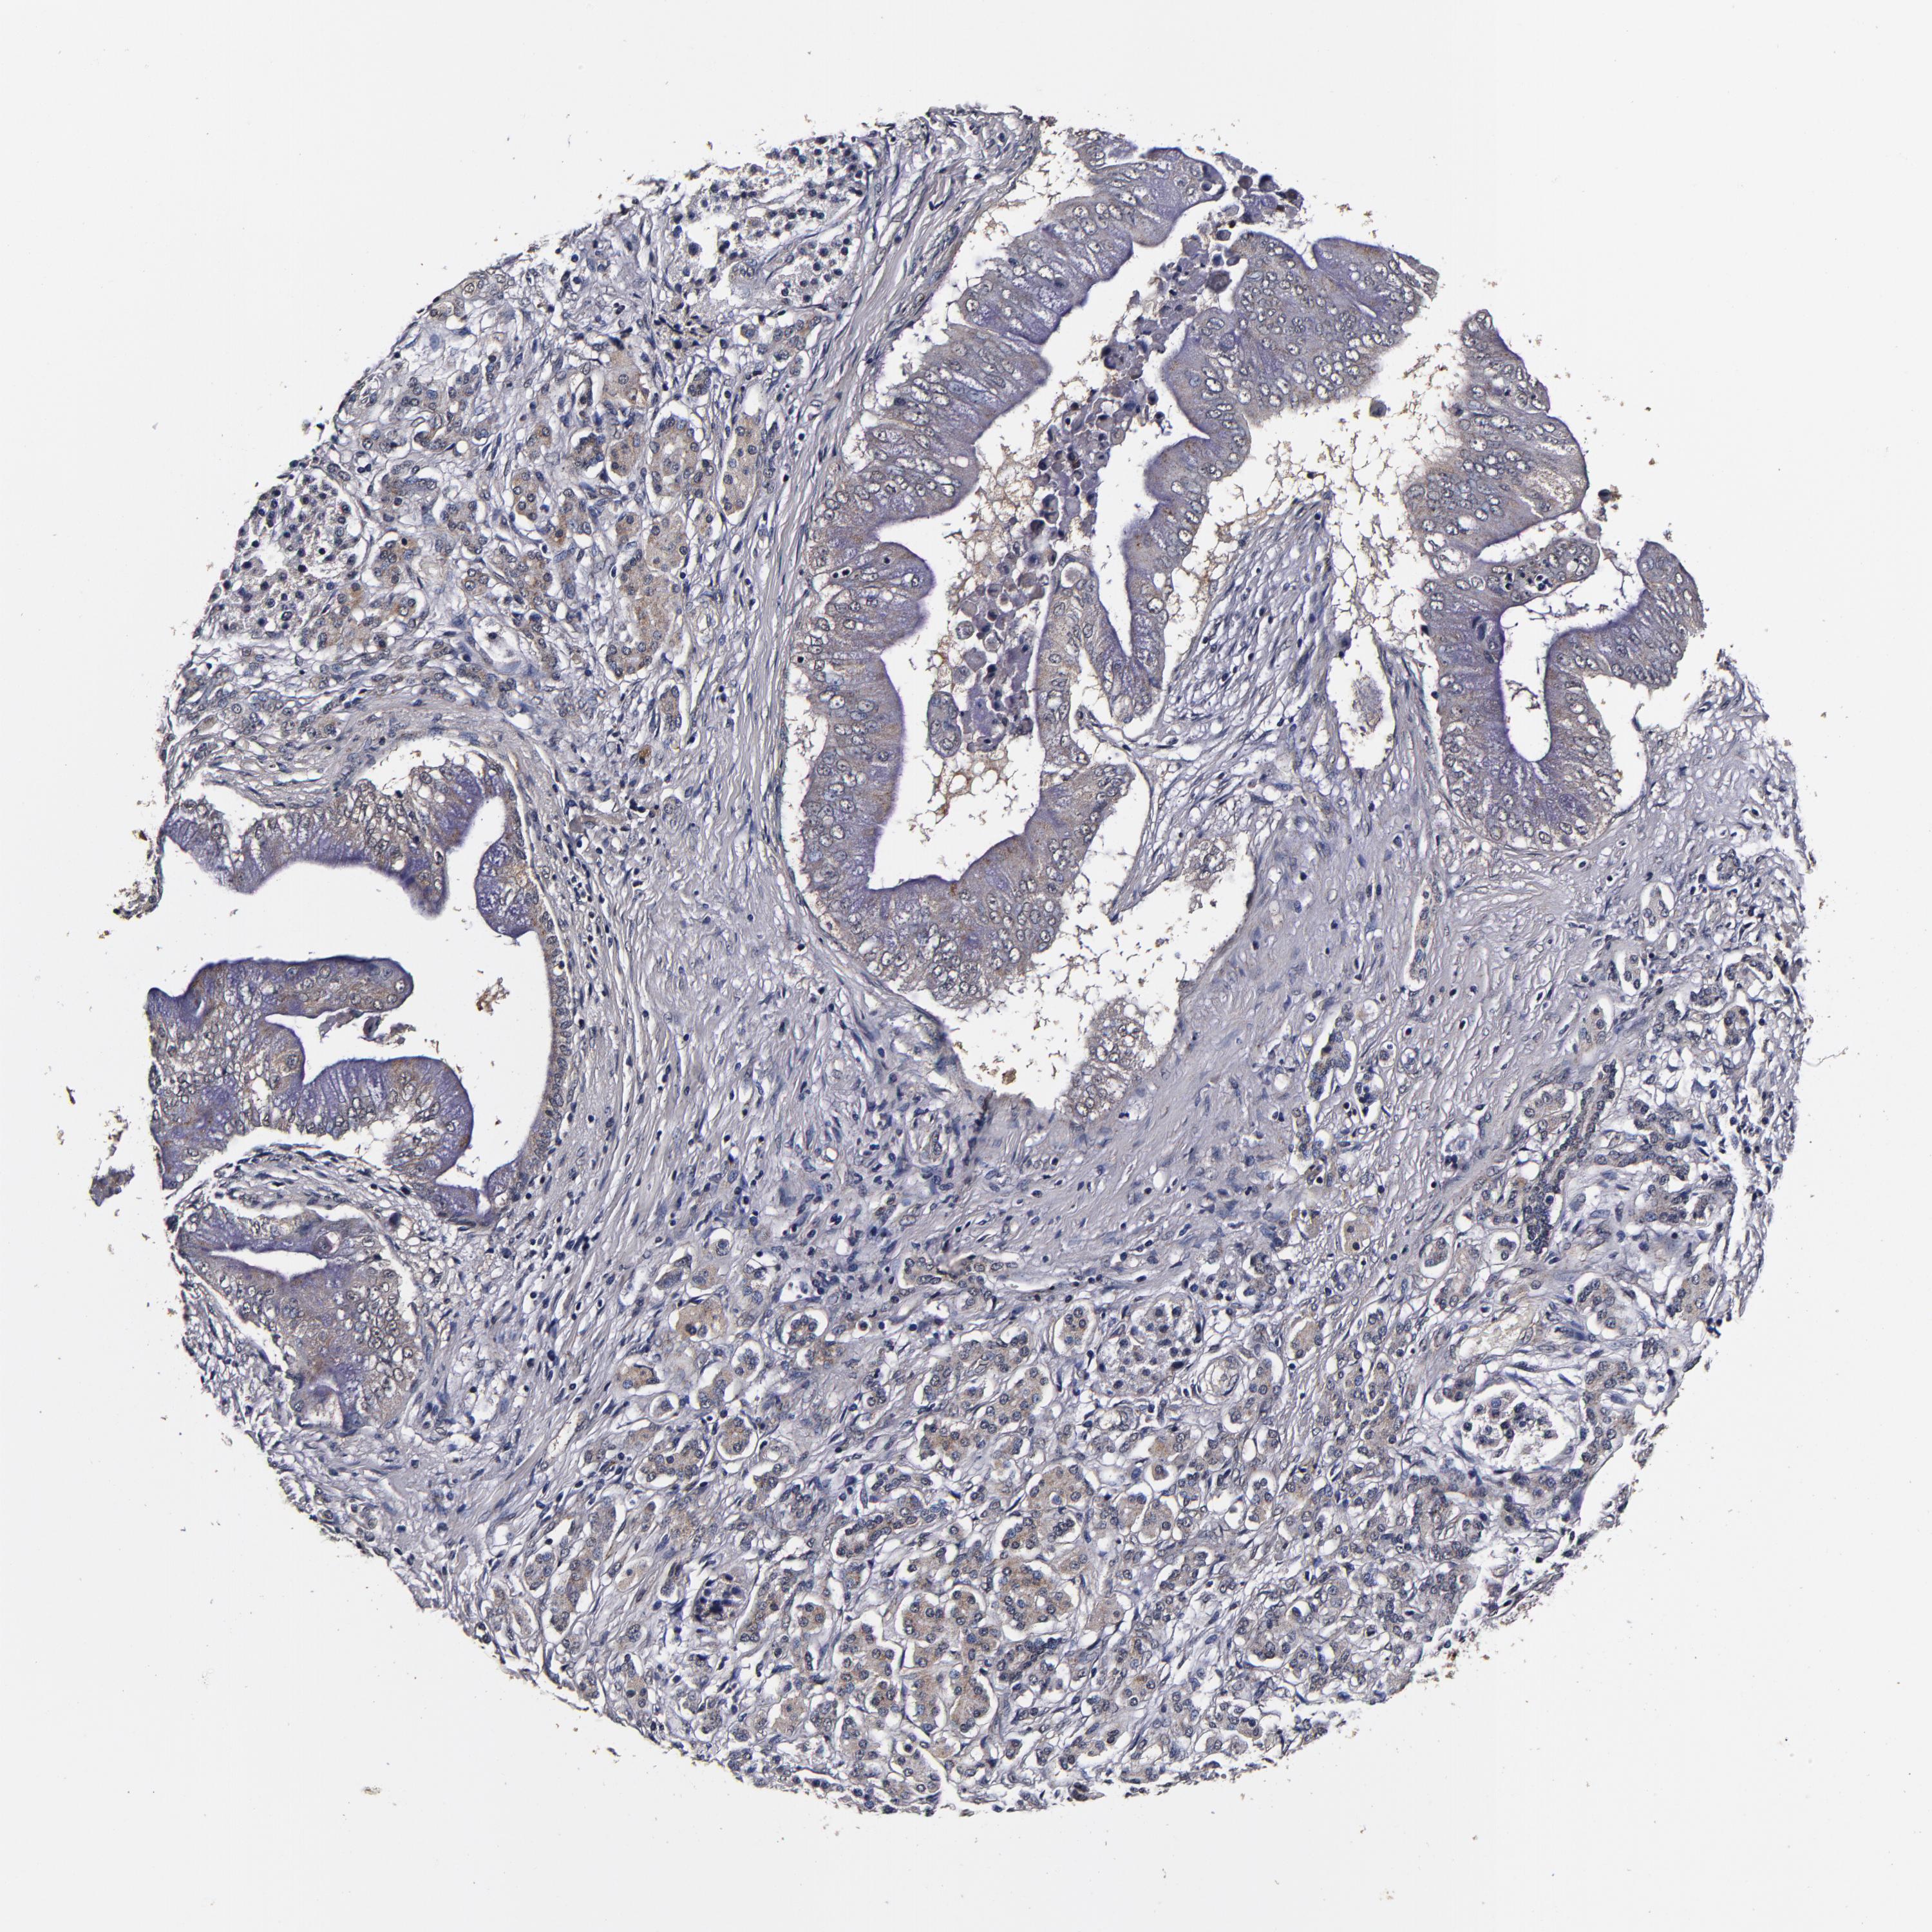

PANCREATIC CANCER - Protein expressioni

A mouse-over function shows sample information and annotation data. Click on an image to view it in a full screen mode. Samples can be filtered based on level of antibody staining by selecting one or several of the following categories: high, medium, low and not detected. The assay and annotation is described here.

Note that samples used for immunohistochemistry by the Human Protein Atlas do not correspond to samples in the TCGA dataset.

Antibody stainingi

Antibody staining in the annotated cell types in the current human tissue is reported as not detected, low, medium, or high, based on conventional immunohistochemistry profiling in selected tissues. This score is based on the combination of the staining intensity and fraction of stained cells.

Each image is clickable and will lead to virtual microscopy that enables deeper exploration of all samples and also displays staining intensity scores, fraction scores and subcellular localization as well as patient and tissue information for each sample.

Antibody HPA040390

Antibody CAB002611

Staining

High

Medium

Low

Not detected

Intensity

Strong

Moderate

Weak

Negative

Quantity

>75%

75%-25%

<25%

None

Location

Nuclear

Cytoplasmic/membranous

Cytoplasmic/membranous,nuclear

Adenocarcinoma, NOS